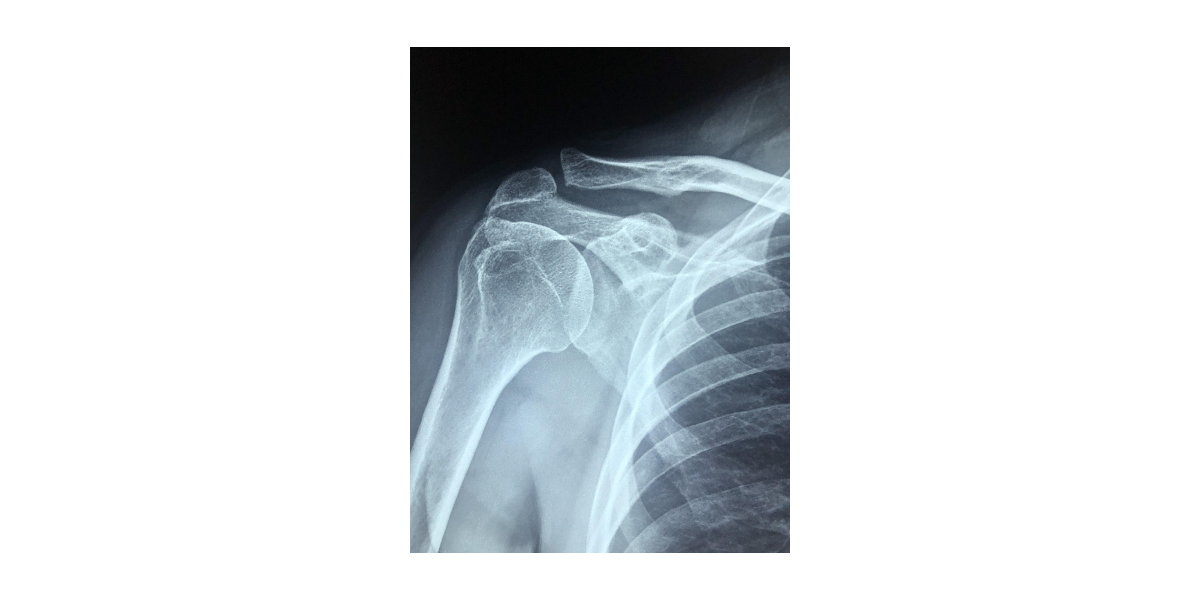

석회성건염의 증상은 다양하지만, 공통적으로 나타나는 주요 증상들이 있습니다. 이 질환은 크게 무증상기, 급성 통증기, 흡수기, 회복기의 네 단계로 나눌 수 있습니다. 각 단계에 따라 증상의 강도와 양상도 다르게 나타납니다. 가장 흔한 증상은 어깨 통증입니다. 특히 밤에 심해지는 통증이 특징이며, 자는 동안 자세를 바꾸기도 어렵고 깊은 수면을 취하기 힘들어집니다. 팔을 머리 위로 올리거나 옷을 입는 등의 일상적인 동작에서도 날카로운 통증이 느껴질 수 있으며, 팔을 들어 올릴 수 없을 정도로 통증이 심한 경우도 많습니다. 또한 움직임 제한이 동반됩니다. 관절의 특정 범위를 넘어서면 심한 통증이 유발되고, 이를 피하기 위해 스스로 움직임을 제한하게 됩니다. 시간이 지날수록 어깨가 굳는 느낌이 들고, 운동 범위가 줄어들며 일상생활에 큰 불편을 초래하게 됩니다. 부기, 열감, 눌렀을 때 통증(압통)도 주요 증상입니다. 염증이 심할 경우 해당 부위가 붓고, 손으로 눌렀을 때 강한 통증이 느껴집니다. 경우에 따라 체온이 약간 오르거나 전신 피로감을 느낄 수 있습니다. 증상이 없는 상태에서도 엑스레이나 초음파 검사로 석회침착이 발견되는 경우가 있습니다. 그러나 석회가 흡수되기 시작하면 심한 통증이 나타나는 급성 흡수기에 접어들게 됩니다. 이 시기에는 많은 환자들이 견딜 수 없는 통증으로 병원을 찾습니다. 이때는 적절한 통증 조절과 염증 치료가 매우 중요합니다. 드물게는 목, 팔, 손까지 통증이 방사되거나 저림 증상이 동반될 수 있으며, 잘못된 진단으로 다른 질환으로 오인되기도 합니다. 따라서 증상이 있다면 조기에 정확한 진단을 받는 것이 필수입니다.